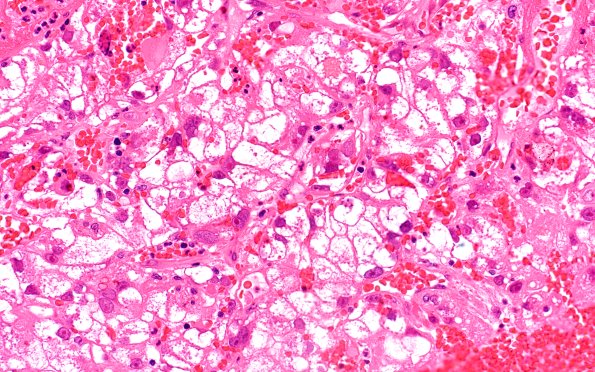

101A2 Metastasis, renal cell (Case 101) H&E 40X

Higher magnification of the tumor in image #101A1. (H&E)